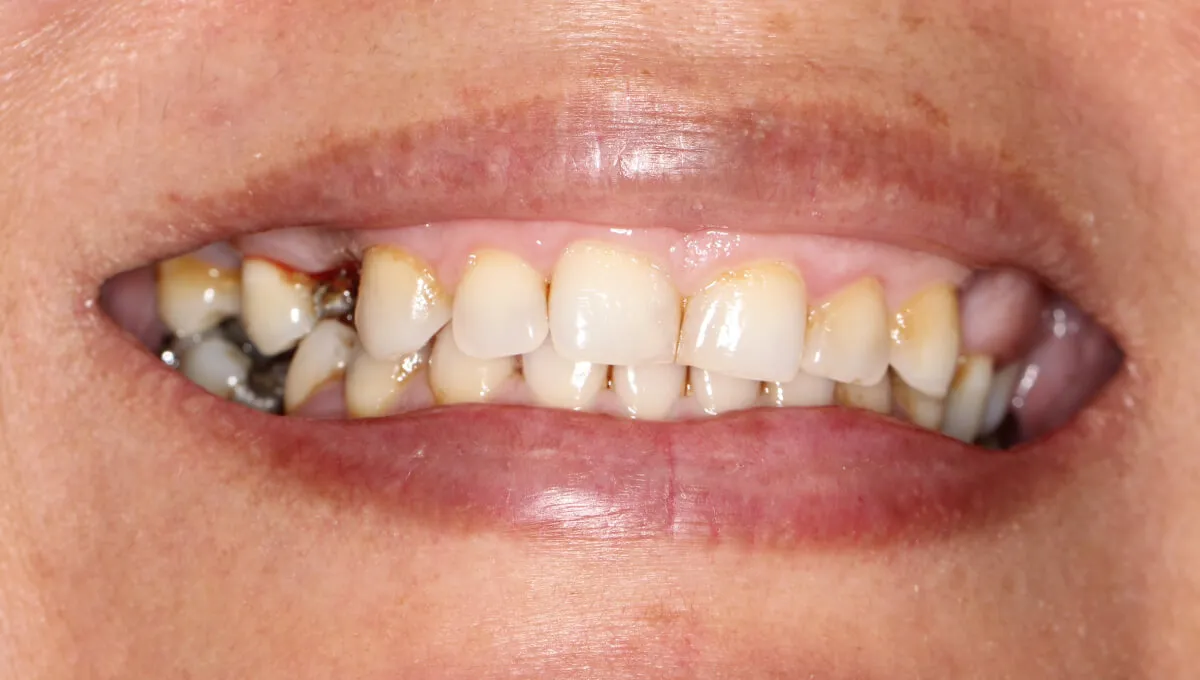

This lady received two dental implants and a bridge to replace her upper missing teeth. We restored her teeth, smile and boosted her confidence. She is very happy with the results and smiles with higher confidence.